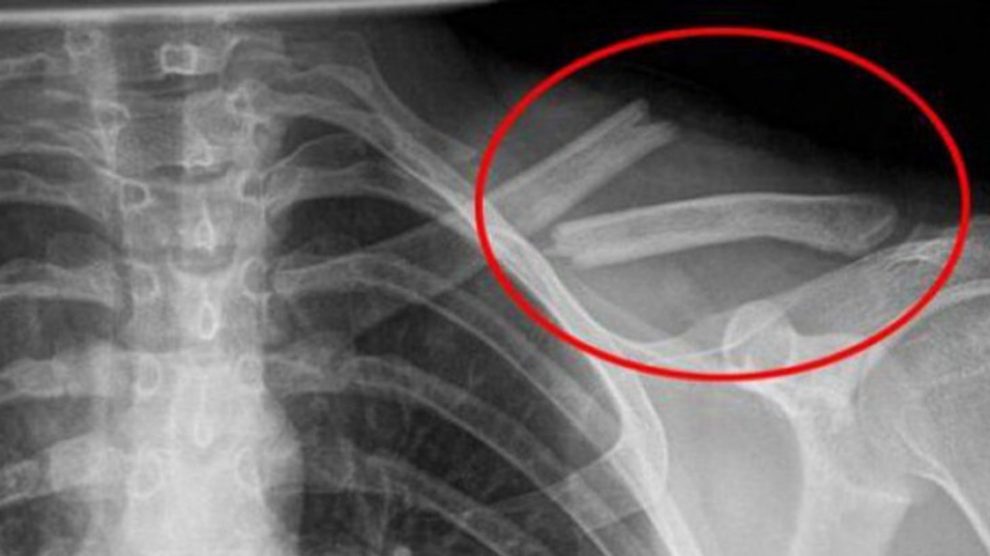

Consumul de băuturi acidulate duce la distrugerea oaselor pe termen lung